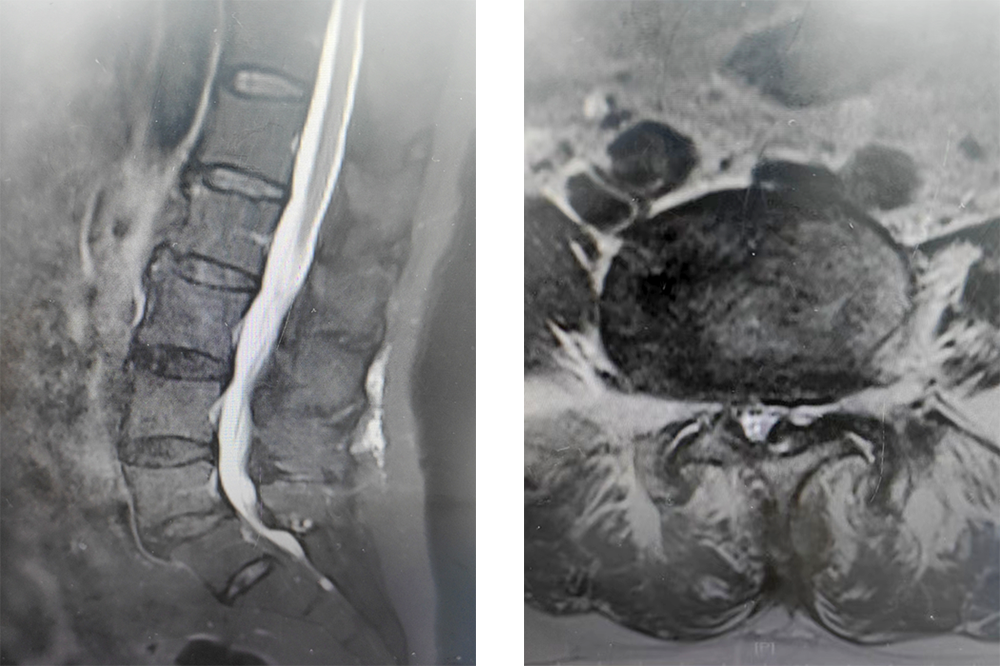

椎間孔鏡下融合手術(shù)

是把因腰椎不穩(wěn)

腰椎滑脫

腰椎管狹窄癥

腰間盤突出伴嚴(yán)重間盤退變等

需要做腰椎融合手術(shù)的人

從過去的開刀手術(shù)

變成在全內(nèi)鏡下微創(chuàng)完成

經(jīng)腰椎后路打開椎管

松解粘連、緊張的神經(jīng)組織

達(dá)到神經(jīng)減壓及椎體間融合

從而解除腰椎滑脫引起的神經(jīng)刺激

重建脊柱穩(wěn)定

術(shù)后影像